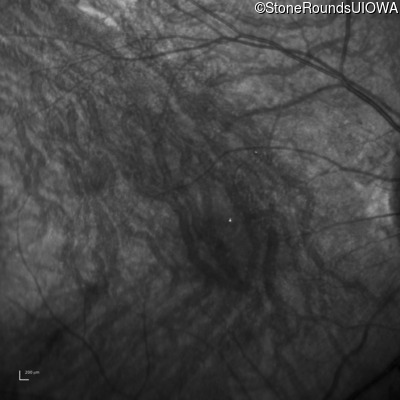

Infrared Fundus Photograph - Right - 10/300 sc

Exemplar